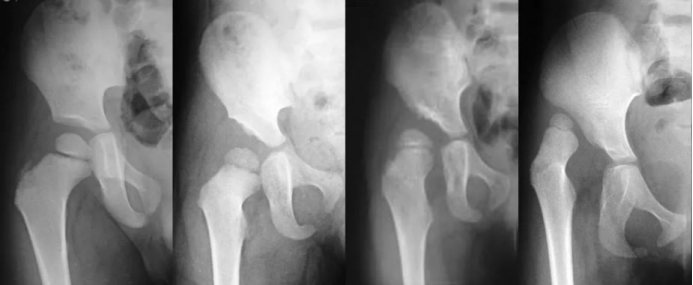

(一)先天性髋关节发育不良(DDH)诊疗

先天性髋关节发育不良是儿童常见骨关节疾病,发病率为0.9‰~3‰,女孩发病率高于男孩,病因可能与分娩方式、人种、遗传及不当包裹方式(迫使髋关节处于伸直位)相关。

诊疗原则:遵循“早诊断、早治疗”理念,出生后3个月内为最佳治疗时期,可通过非手术方式实现良好干预;

技术支撑:借助3D打印导板制导脊柱手术、髋关节手术定位及辅助术中操作,提升手术精准度。